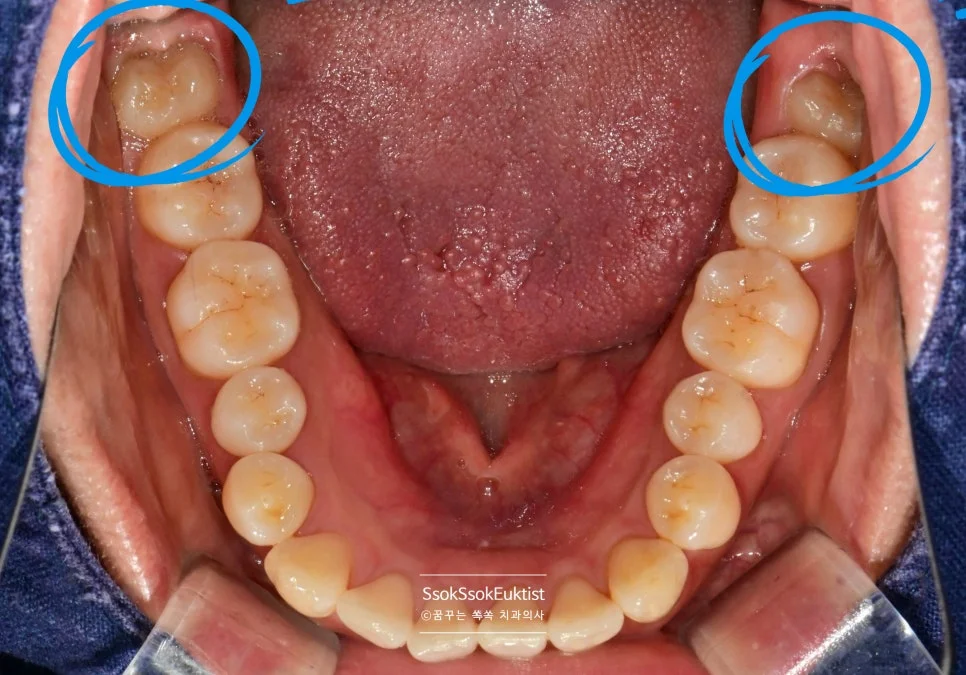

구내 사진으로 확인한 하악 사랑니 상태

하악 교합면 구내사진 양쪽 매복 사랑니 파란 원 표시

하악 교합면 구내사진 — 양쪽 매복 사랑니(파란 원) 확인

아래쪽 사랑니는 매복 된 사랑니로, 위쪽 사랑니보다 발치 시 더 높은 난도가 요구됩니다.